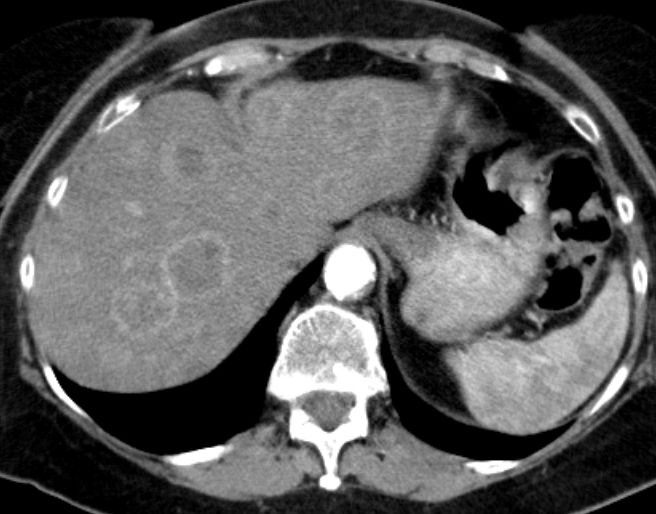

Magen 62-jährige Frau mit kolikartigen Flankenschmerzen durch einen mittlerer Harnleiterstein. Bei der Durchuntersuchung fand sich eine verdickte Magenwand. Endoskopisch chronische, nicht aktive Entzündung mit foveolärer Hyperplasie. Die Biopsie ergab Infiltrate eines gering differenzierten neuroendokrinen Karzinoms (G3, Ki 67 40%). Bekannte Haemangiome der Leber.